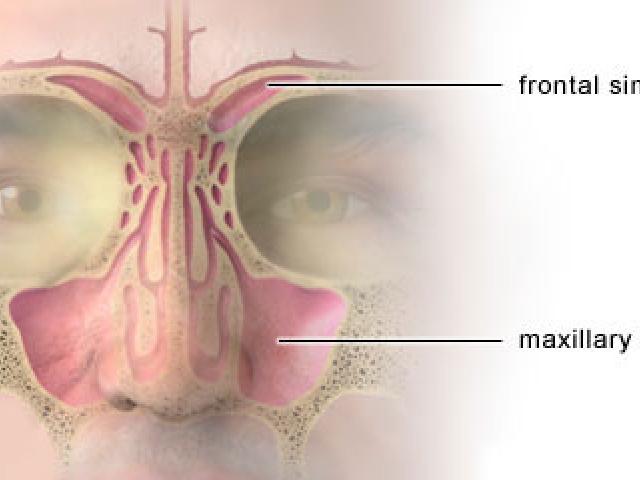

Estornudar es un síntoma común cuando las personas tienen un resfriado, pero ¿qué pasa cuando las personas estornudan mucho sin estar resfriadas?